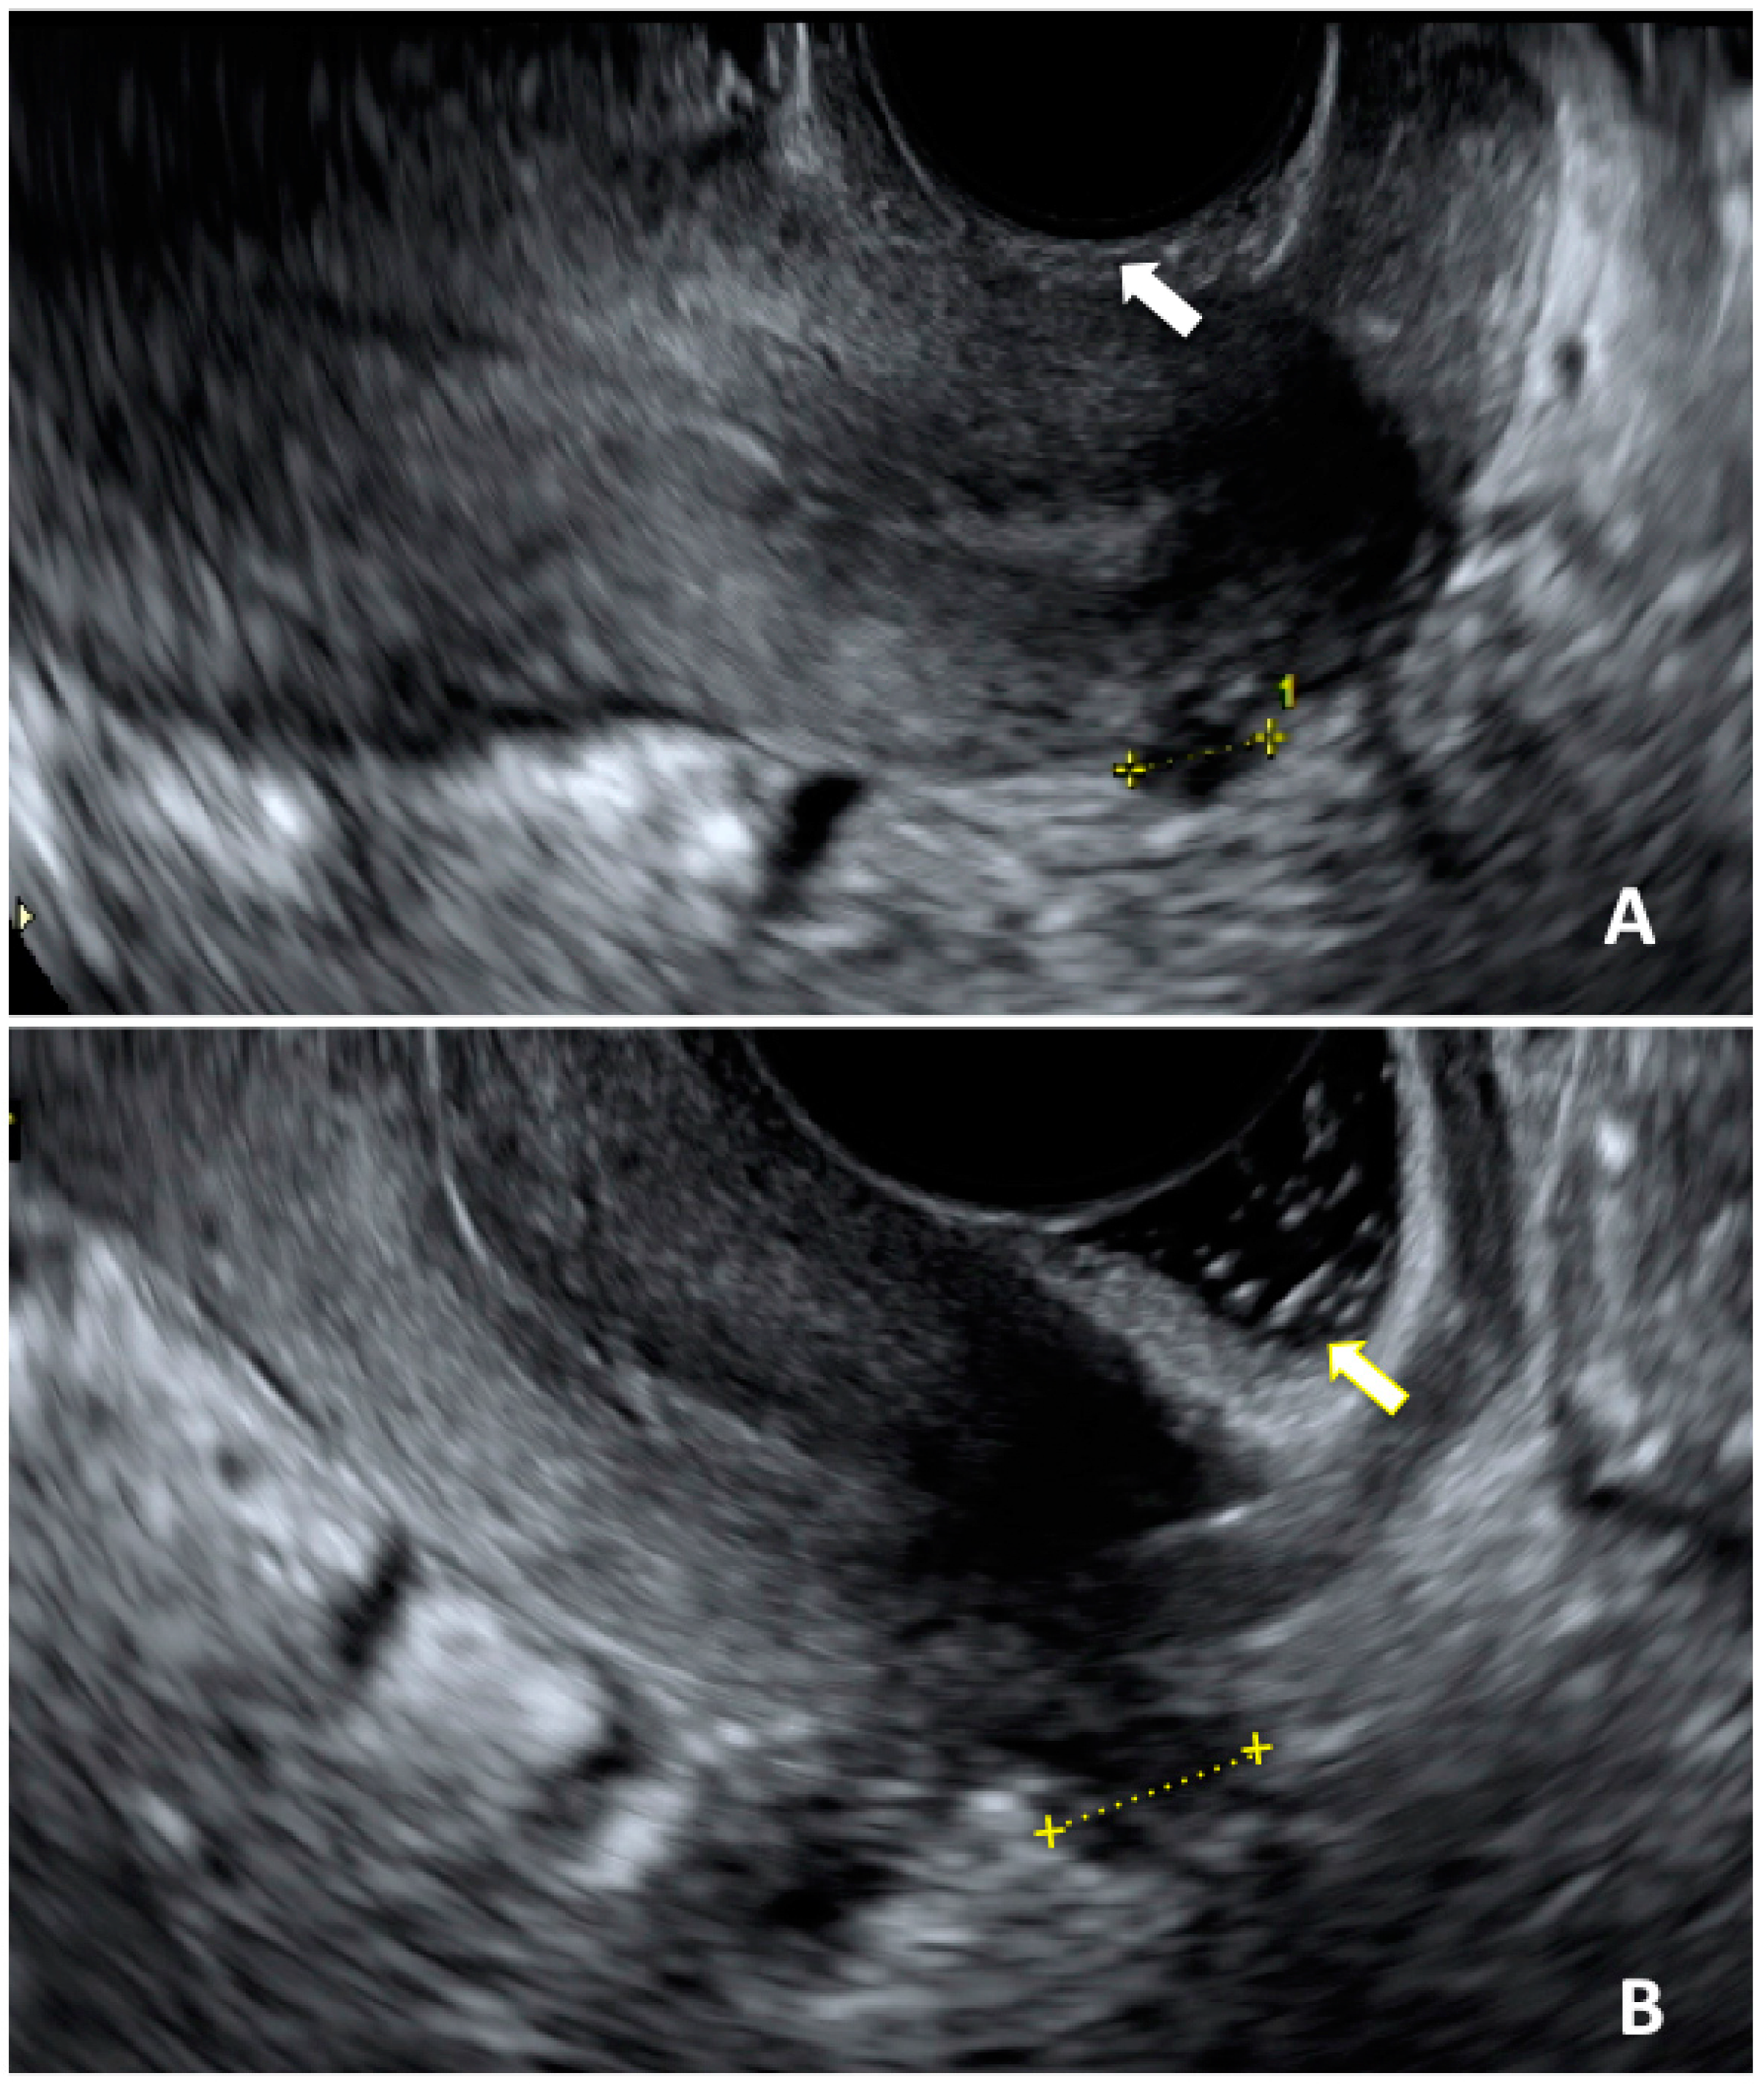

- Martire, F.G.; Lazzeri, L.; Conway, F.; Siciliano, T.; Pietropolli, A.; Piccione, E.; Solima, E.; Centini, G.; Zupi, E.; Exacoustos, C. Adolescence and endometriosis: Symptoms, ultrasound signs and early diagnosis. Fertil. Steril. 2020, 114, 1049–1057. [Google Scholar] [CrossRef]

- Martire, F.G.; Russo, C.; Selntigia, A.; Nocita, E.; Soreca, G.; Lazzeri, L.; Zupi, E.; Exacoustos, C. Early noninvasive diagnosis of endometriosis: Dysmenorrhea and specific ultrasound findings are important indicators in young women. Fertil. Steril. 2023, 119, 455–464. [Google Scholar] [CrossRef]

- Hudelist, G.; Ballard, K.; English, J.; Wright, J.; Banerjee, S.; Mastoroudes, H.; Thomas, A.; Singer, C.F.; Keckstein, J. Transvaginal sonography vs. clinical examination in the preoperative diagnosis of deep infiltrating endometriosis. Ultrasound Obstet. Gynecol. 2011, 37, 480–487. [Google Scholar] [CrossRef]

- Hudelist, G.; Fritzer, N.; Staettner, S.; Tammaa, A.; Tinelli, A.; Sparic, R.; Keckstein, J. Uterine sliding sign: A simple sonographic predictor for presence of deep infiltrating endometriosis of the rectum. Ultrasound Obstet. Gynecol. 2013, 41, 692–695. [Google Scholar] [CrossRef] [PubMed]